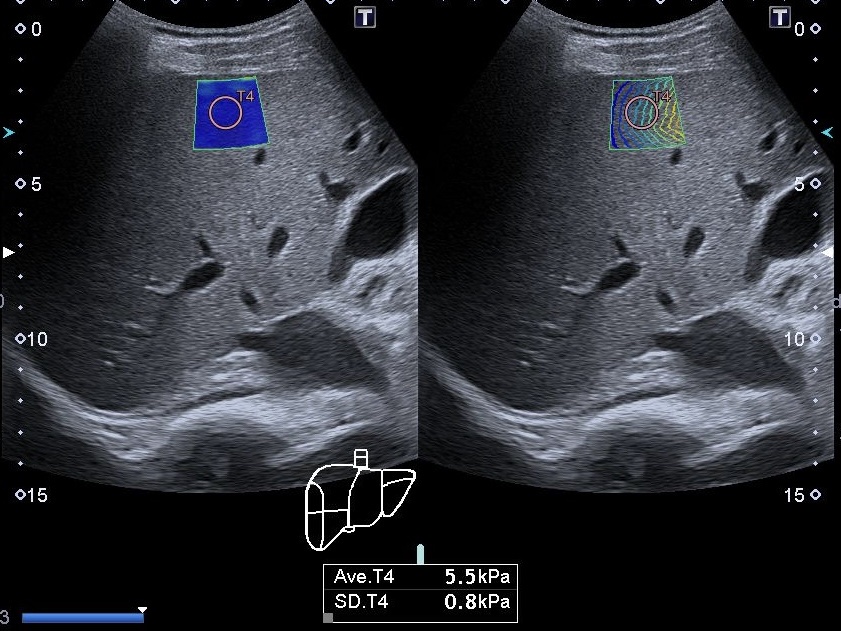

Еластографія печінки Київ – це метод діагностики, який використовується для оцінки ступеня фіброзу (жирової дегенерації) печінки. Цей метод ґрунтується на...